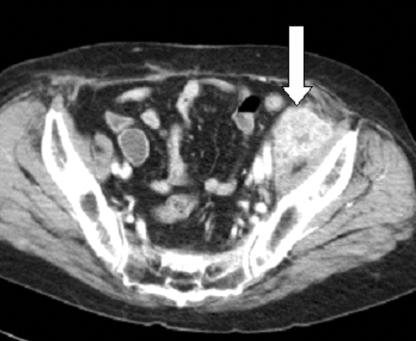

Iatrogenic implantation has been the main cause in the majority of cases of transitional call carcinoma (TCC) with metastasis to the abdominal wall. A 66-year-old woman had undergone radical cystectomy 20 years prior to presenting. Radiological investigations revealed one mass in the left lower abdominal wall and one mass in the right inguinal area. She underwent wide excision of the lesions that revealed metastasis of TCC. This report describes this case of a woman with bladder carcinoma who developed a metastasis in the anterior abdominal wall following an apparent disease-free interval of 20 years.

医源性植入是大多数发生腹壁转移的移行性上皮癌(TCC)病例的主要原因。一名66岁女性在就诊前20年接受了根治性膀胱切除术。影像学检查发现左下腹壁有一个肿块,右腹股沟区有一个肿块。她接受了病变的广泛切除,结果显示为TCC转移。本报告描述了一名膀胱癌女性患者的病例,该患者在经历了20年的无病期后,在前腹壁发生了转移。